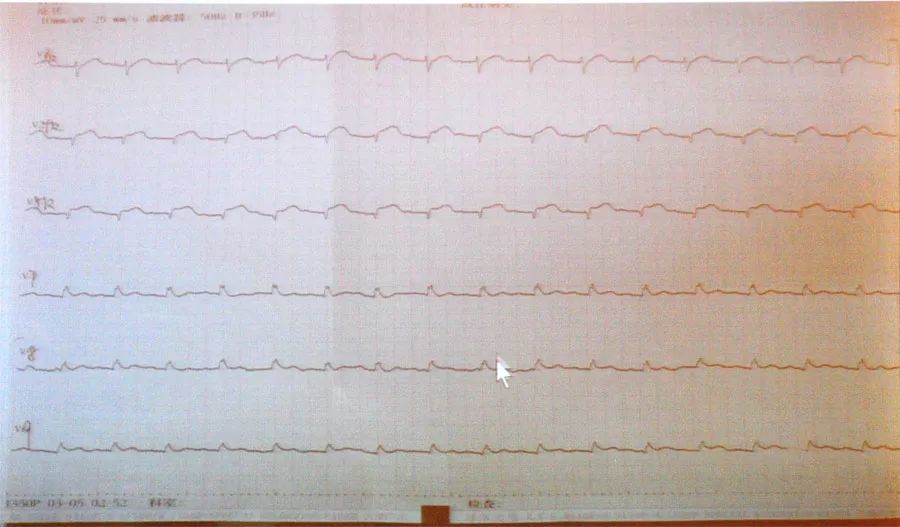

心肌供血不足心电图

心肌供血不足心电图,心脏供血不足心电图